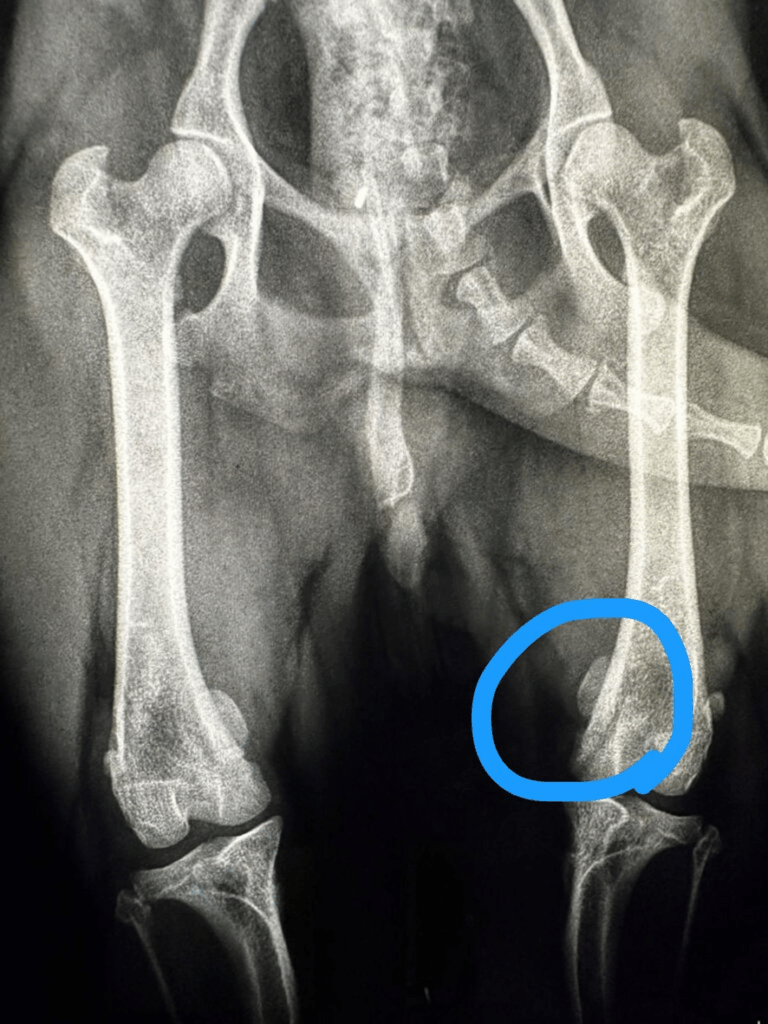

とのことで整形専門外来に受診されました。検査をしていき膝蓋骨内方脱臼(パテラ)と診断になりました。

飼い主様に1から現在起きている状態をご説明させていただき、飼い主様が治してあげられるのであればこのこのために治してあげたい。ということで手術を希望されました。

当院では片足ずつ手術を行い現在ではとても元気に走り回りすごしています。

- 大腿骨(モモの骨)や脛骨(すねの骨)の変形が進行

多くの場合、大腿骨や脛骨の角度・筋肉のバランス・滑車溝の深さなど、骨格全体の問題が関わっています。

パテラの手術は以下のような要素を組み合わせて行う必要があります:

- 滑車溝形成(溝を深くする)

- 脛骨粗面転移術(膝蓋骨を正しい位置に引っ張る)

- 軟部組織の縫縮術(内外側の靭帯バランス調整)

これらを個々の骨格・グレードに合わせて正確に設計・実行する技術力が必要です。